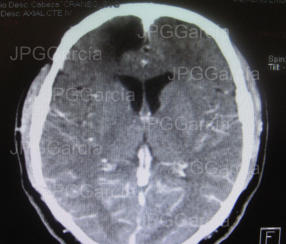

Estudio tomográfico prequirúrgico

Resultado de tomografía craneal postquirúrgica en donde se observa drenaje del absceso cerebral